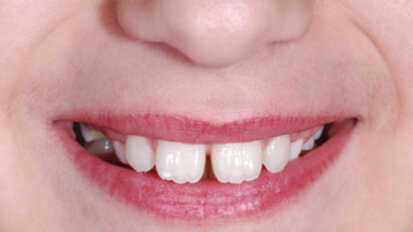

Retence získává nový význam